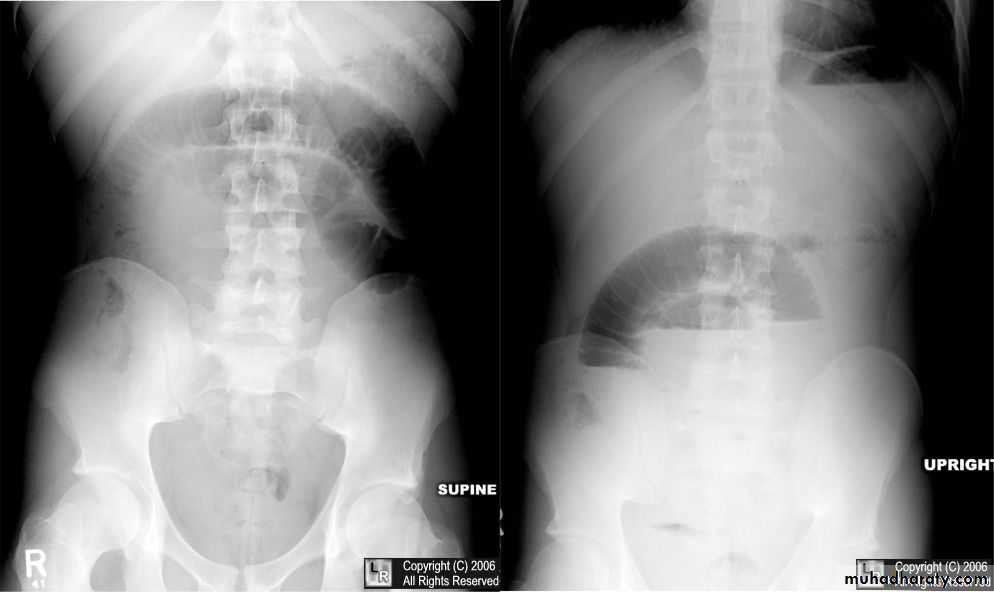

Bowel obstruction

Plain x ray SBOdilated loops with air fluid level in erect position

centrally placed

transverse lines (circular folds ) valvule convent's

Plain x ray LBO

dilated bowel with gasperipheral

haustra (not lines across bowel)

may have cut-off point